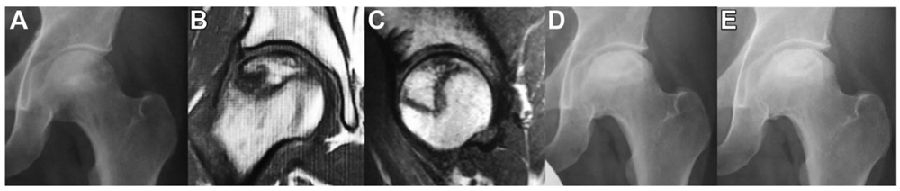

图9.一例股骨头坏死患者影像学资料

(A)第一次就诊时,42岁男性股骨头出现症状性左侧骨坏死。(B) T1磁共振成像(MRI)冠状面。(C) MRI矢状面显示62.1%股骨头前后(AP)坏死灶。(D) x线片显示首次就诊后3年的塌陷< 3mm。(E) x线片显示首次就诊5年后股骨头左侧骨坏死(ONFH)塌陷停止。